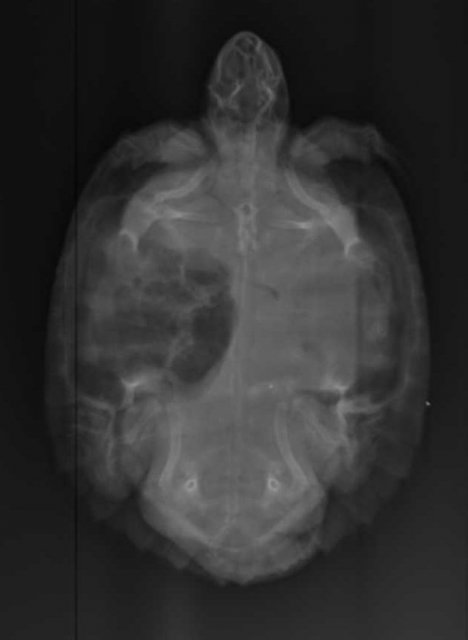

Алексей Alex-Raduga Ваше имя: Алексей Локация: Россия, МО, Серпуховский район Опубликовано: 31 января 2024 Автор Опубликовано: 31 января 2024 @moth здравствуйте ! Сегодня возил на рентген, сделали все проекции, Савина сказала - возможно пневмония, назначила антибиотик энрофлоксацин 2,5%, по 0,12мл 3-4 раза через день и элеовит 0,18мл. - 2 раза с интервалом в 14 дней. Также остается эспусмизан еще 14-21 день (21 день уже его давал, с кормом раз в 3 дня). Также назначила взять анализ кала. Если не пройдет - сказала везти на КТ. Все верно, больше ничего пока не нужно ?

Консультанты moth Ваше имя: Мария Локация: Москва Опубликовано: 31 января 2024 Консультанты Опубликовано: 31 января 2024 @Алексей Alex-Raduga да, всё верно одно лёгкое мутное совсем, жалко тогда она не стала другие проекции делать. А Элеовит ему делали раньше?

Консультанты moth Ваше имя: Мария Локация: Москва Опубликовано: 8 февраля 2024 Консультанты Опубликовано: 8 февраля 2024 @Алексей Alex-Raduga она сказала, что тут однозначно кт нужно. Либо лёгкое схлопнулось, либо сильная односторонняя пневмония. Трава с мостика такое бы не вызвала.

Алексей Alex-Raduga Ваше имя: Алексей Локация: Россия, МО, Серпуховский район Опубликовано: 15 февраля 2024 Автор Опубликовано: 15 февраля 2024 (изменено) Результаты Кт : Протокол КТ Информация по животному Тотоша ,рептилия ,Черепаха красноухая. Протокол ДЫХАТЕЛЬНЫЕ ПУТИ - Визуализируется короткая трахея, разделяющаяся на два бронха, делающие изгиб в дорсальном направлении и входящие в легкие. Правое легкое имеет типичный сегментированный многокамерный вид, пневматизировано, имеет ретикулярный и "сотовый" рисунок, определяется умеренное утолщение перегородок. Бронх левого легкого частично пневматизирован, на остальном протяжении заполнен мягкотканым патологическим содержимым. Левое легкое уменьшено (25х16х12 мм), безвоздушно, паренхима уплотнена до мягкотканых значений, перфузия сохранена, слабо неравномерная. КОСТНЫЕ СТРУКТУРЫ - без патологических изменений. СЕРДЦЕ - без патологических изменений. ПЕЧЕНЬ - без патологических изменений. ЖЕЛЧНЫЙ ПУЗЫРЬ - в правой доле печени, грушевидной формы, умеренно наполнен однородным жидкостным содержимым. СЕЛЕЗЕНКА - овальной формы, 12 мм, расположена дорсо-медиально от желудка. ПОДЖЕЛУДОЧНАЯ ЖЕЛЕЗА - не визуализируется. ЖЕЛУДОК - не наполнен, стенки не утолщены. КИШЕЧНИК - содержит минимальное количество химуса и газ, стенки не утолщены. ПОЧКИ - локализованы в дорсальной части каудального целома, структура и перфузия не изменены. МОЧЕВОЙ ПУЗЫРЬ - умеренно наполнен, стенки не изменены. ПОЛОВЫЕ ОРГАНЫ - не визуализируются. Заключение Заключение: КТ-признаки тотальной левосторонней пневмонии. Обструкция левого бронха. Информация по животномуТотоша ,рептилия ,Черепаха красноухая Анамнез: В мире животнрых (Серпухов) Савина Ярослава Игоревна Жалоба - в течении месяца всплывает на одну сторону (правую). Бывли в сторонней клинике - назначили антибиотик, газасвязывающий препарат, витамины. Активность - норма. Аппетит - норма. Дефекация - норма. Кормление - корм для черепах. Содержание - аквариум, вода 26-27 гр, мостик, УФ лампа и лампа нагрева. Объективно: Общее состояние - удовлетворительное на момент осмотра. Ментальный статус - ясный. Дегидратация - не выражена. Глаза - чистые. Носовые ходы - чистые. Ротовая полость - без патологий. ВСО - бледно-розовые. Состояние кожного покрова и панциря - линька. Упитанность - норма. М - 272 гр. Диагнозы: Предварительный диагноз: Пневмония Врач: Ложечко Анастасия Леонидовна А НАЗНАЧЕНИЙ НЕТ ! Чем лечить-то ? Продолжить уколы энрофлоксацина ? Изменено 15 февраля 2024 пользователем Алексей Alex-Raduga